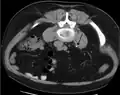

Imaging studies

Calcium-containing stones are relatively radiodense (opaque to X-rays), and they can often be detected by a traditional radiography of the abdomen that includes the kidneys, ureters, and bladder (KUB film).[59] KUB radiography, although useful in monitoring size of stone or passage of stone in stone formers, might not be useful in the acute setting due to low sensitivity.[60] Some 60% of all renal stones are radiopaque.[61][62] In general, calcium phosphate stones have the greatest density, followed by calcium oxalate and magnesium ammonium phosphate stones. Cystine calculi are only faintly radiodense, while uric acid stones are usually entirely radiolucent.[63]

In people with a history of stones, those who are less than 50 years of age and are presenting with the symptoms of stones without any concerning signs do not require helical CT scan imaging.[64] A computed tomography (CT) scan is also not typically recommended in children.[65]

Otherwise a noncontrast helical CT scan with 5 millimeters (0.2 in) sections is the diagnostic method to use to detect kidney stones and confirm the diagnosis of kidney stone disease.[16][57][61][66][7] Near all stones are detectable on CT scans with the exception of those composed of certain drug residues in the urine,[59] such as from indinavir.

Where a CT scan is unavailable, an intravenous pyelogram may be performed to help confirm the diagnosis of urolithiasis. This involves intravenous injection of a contrast agent followed by a KUB film. Uroliths present in the kidneys, ureters, or bladder may be better defined by the use of this contrast agent. Stones can also be detected by a retrograde pyelogram, where a similar contrast agent is injected directly into the distal ostium of the ureter (where the ureter terminates as it enters the bladder).[61]

Renal ultrasonography can sometimes be useful, because it gives details about the presence of hydronephrosis, suggesting that the stone is blocking the outflow of urine.[59] Radiolucent stones, which do not appear on KUB, may show up on ultrasound imaging studies. Other advantages of renal ultrasonography include its low cost and absence of radiation exposure. Ultrasound imaging is useful for detecting stones in situations where X-rays or CT scans are discouraged, such as in children or pregnant women.[67] Despite these advantages, renal ultrasonography in 2009 was not considered a substitute for noncontrast helical CT scan in the initial diagnostic evaluation of urolithiasis.[66] The main reason for this is that, compared with CT, renal ultrasonography more often fails to detect small stones (especially ureteral stones) and other serious disorders that could be causing the symptoms.[14]